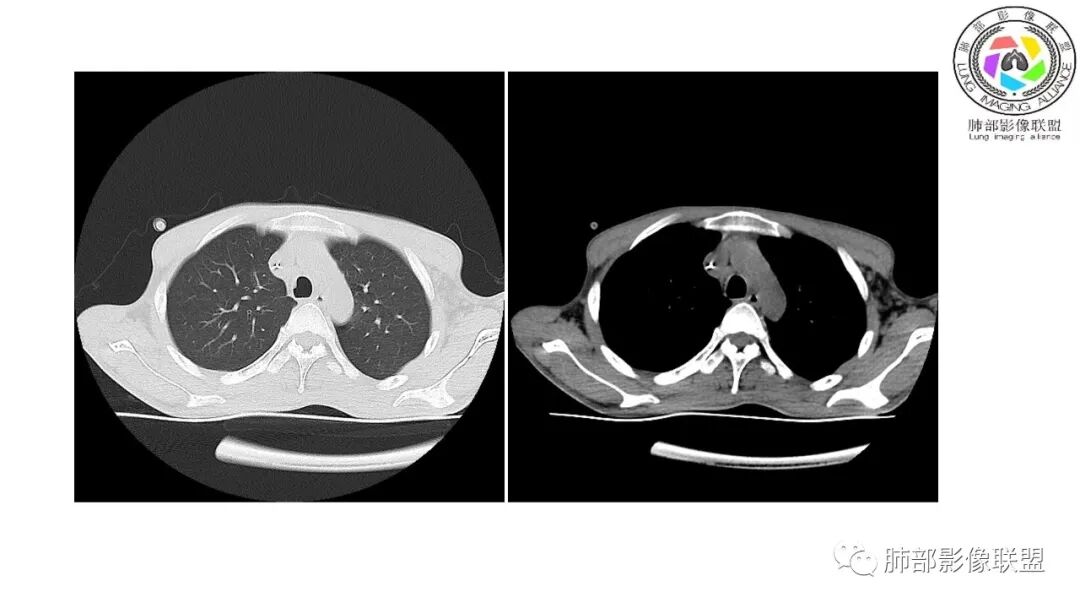

影像与临床:1.青年男性,HlV阳性,颜面部皮疹(未提供皮疹图像)、发热(高热),实验室CRP、PCT高,T-Spot阴性。2.右肺下叶空洞结节,壁厚不均,边界清楚,其内线状影,未见液平及钙化,未见卫星灶,纵隔淋巴结增大,双侧腋窝见增大淋巴结。心腔内低密度提示贫血可能。肝脾影增大,未见结节影及块影。腹膜后见多发增大淋巴结。

综合分析:本例肺部影像学改变并不具有特征性,空洞性病灶须与多种疾病鉴别,但年轻HIV阳性患者,高热,皮疹,肝脾增大,纵隔、腋窝、腹膜后见多发增大淋巴结等都强烈提示马尔尼菲篮状菌感染的可能性。